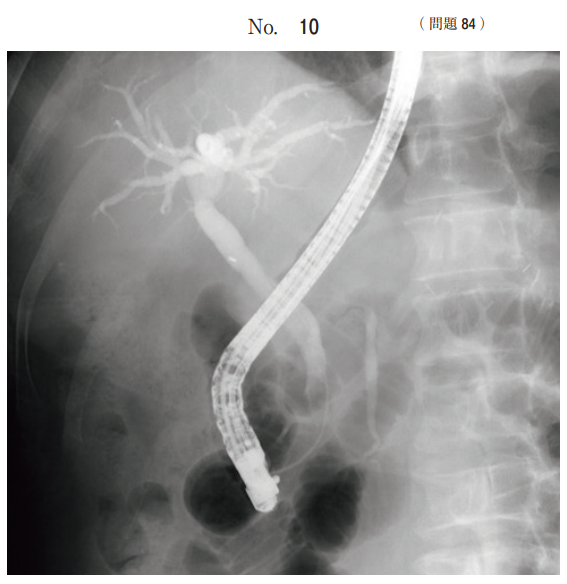

腹部の造影画像(別冊No. 10)を別に示す。

検査法で正しいのはどれか。

1.DIC

2.DIP

3.ERCP

4.MRCP

5.PTC